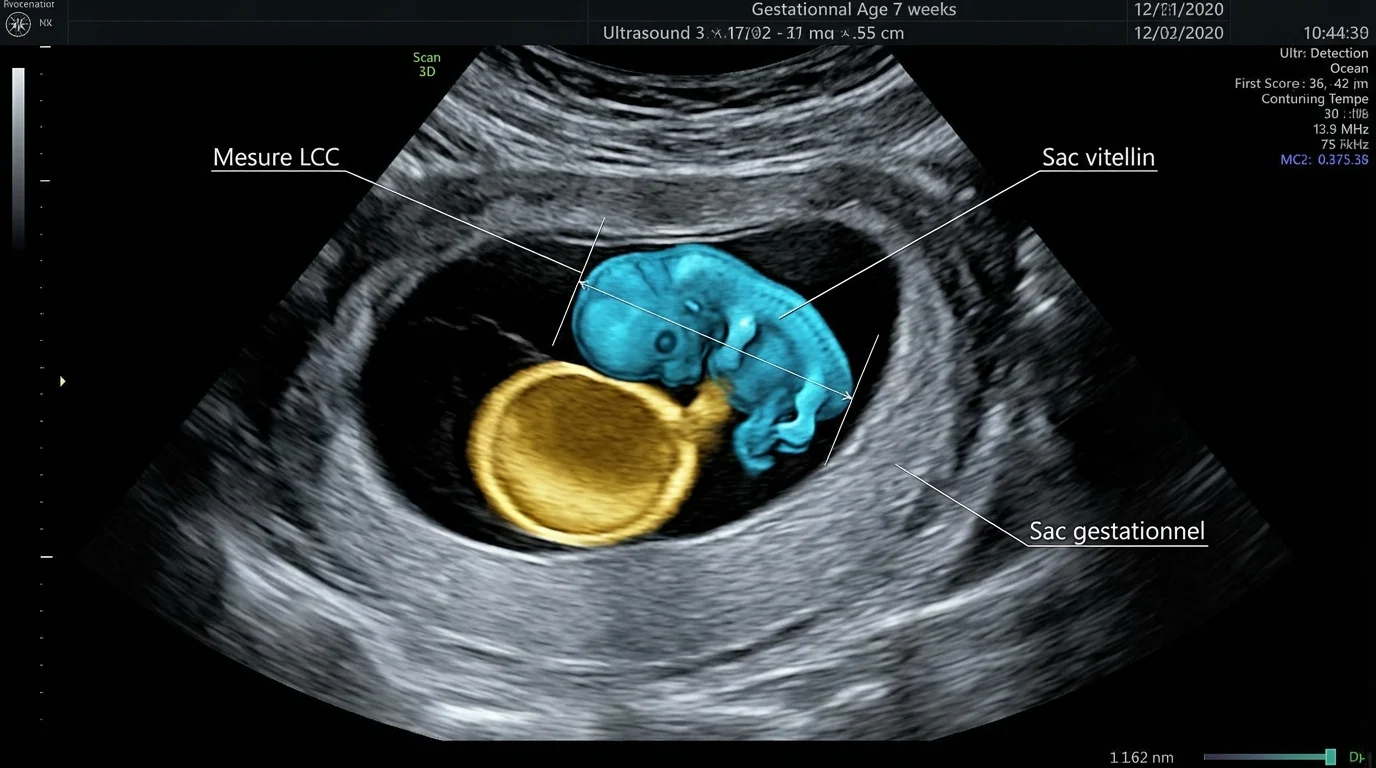

Disons les choses : à 7 SA, votre embryon fait la taille d'une framboise. Une erreur de placement du curseur de 1,2 mm sur l'écran peut décaler la datation de 3 à 4 jours. Selon les données de la Fédération Française d'Échographie de 2026, la marge d'erreur acceptée est de 15,2% sur ces mesures précoces. Il suffit que l'embryon soit mal orienté pour que la mesure soit sous-estimée.

Le tableau comparatif des mesures à 7 SA

Voici les repères techniques utilisés par les praticiens en 2026 pour évaluer la croissance.

| Stade de grossesse | Longueur Cranio-Caudale (LCC) | Rythme cardiaque attendu |

|---|---|---|

| 6 SA + 4 jours | 7 à 9 mm | 110-130 bpm |

| 7 SA pile | 10 à 12 mm | 130-150 bpm |

| 7 SA + 4 jours | 13 à 15 mm | 145-160 bpm |

Le décalage entre le sac et l'embryon

Un indicateur souvent oublié est l'espace entre la paroi du sac gestationnel et l'embryon. Si cet espace est inférieur à 5 mm (ce qu'on appelle un petit sac), le risque de fausse couche au premier trimestre grimpe à 74%. C'est une donnée technique que peu de parents connaissent mais qui alerte immédiatement les radiologues.